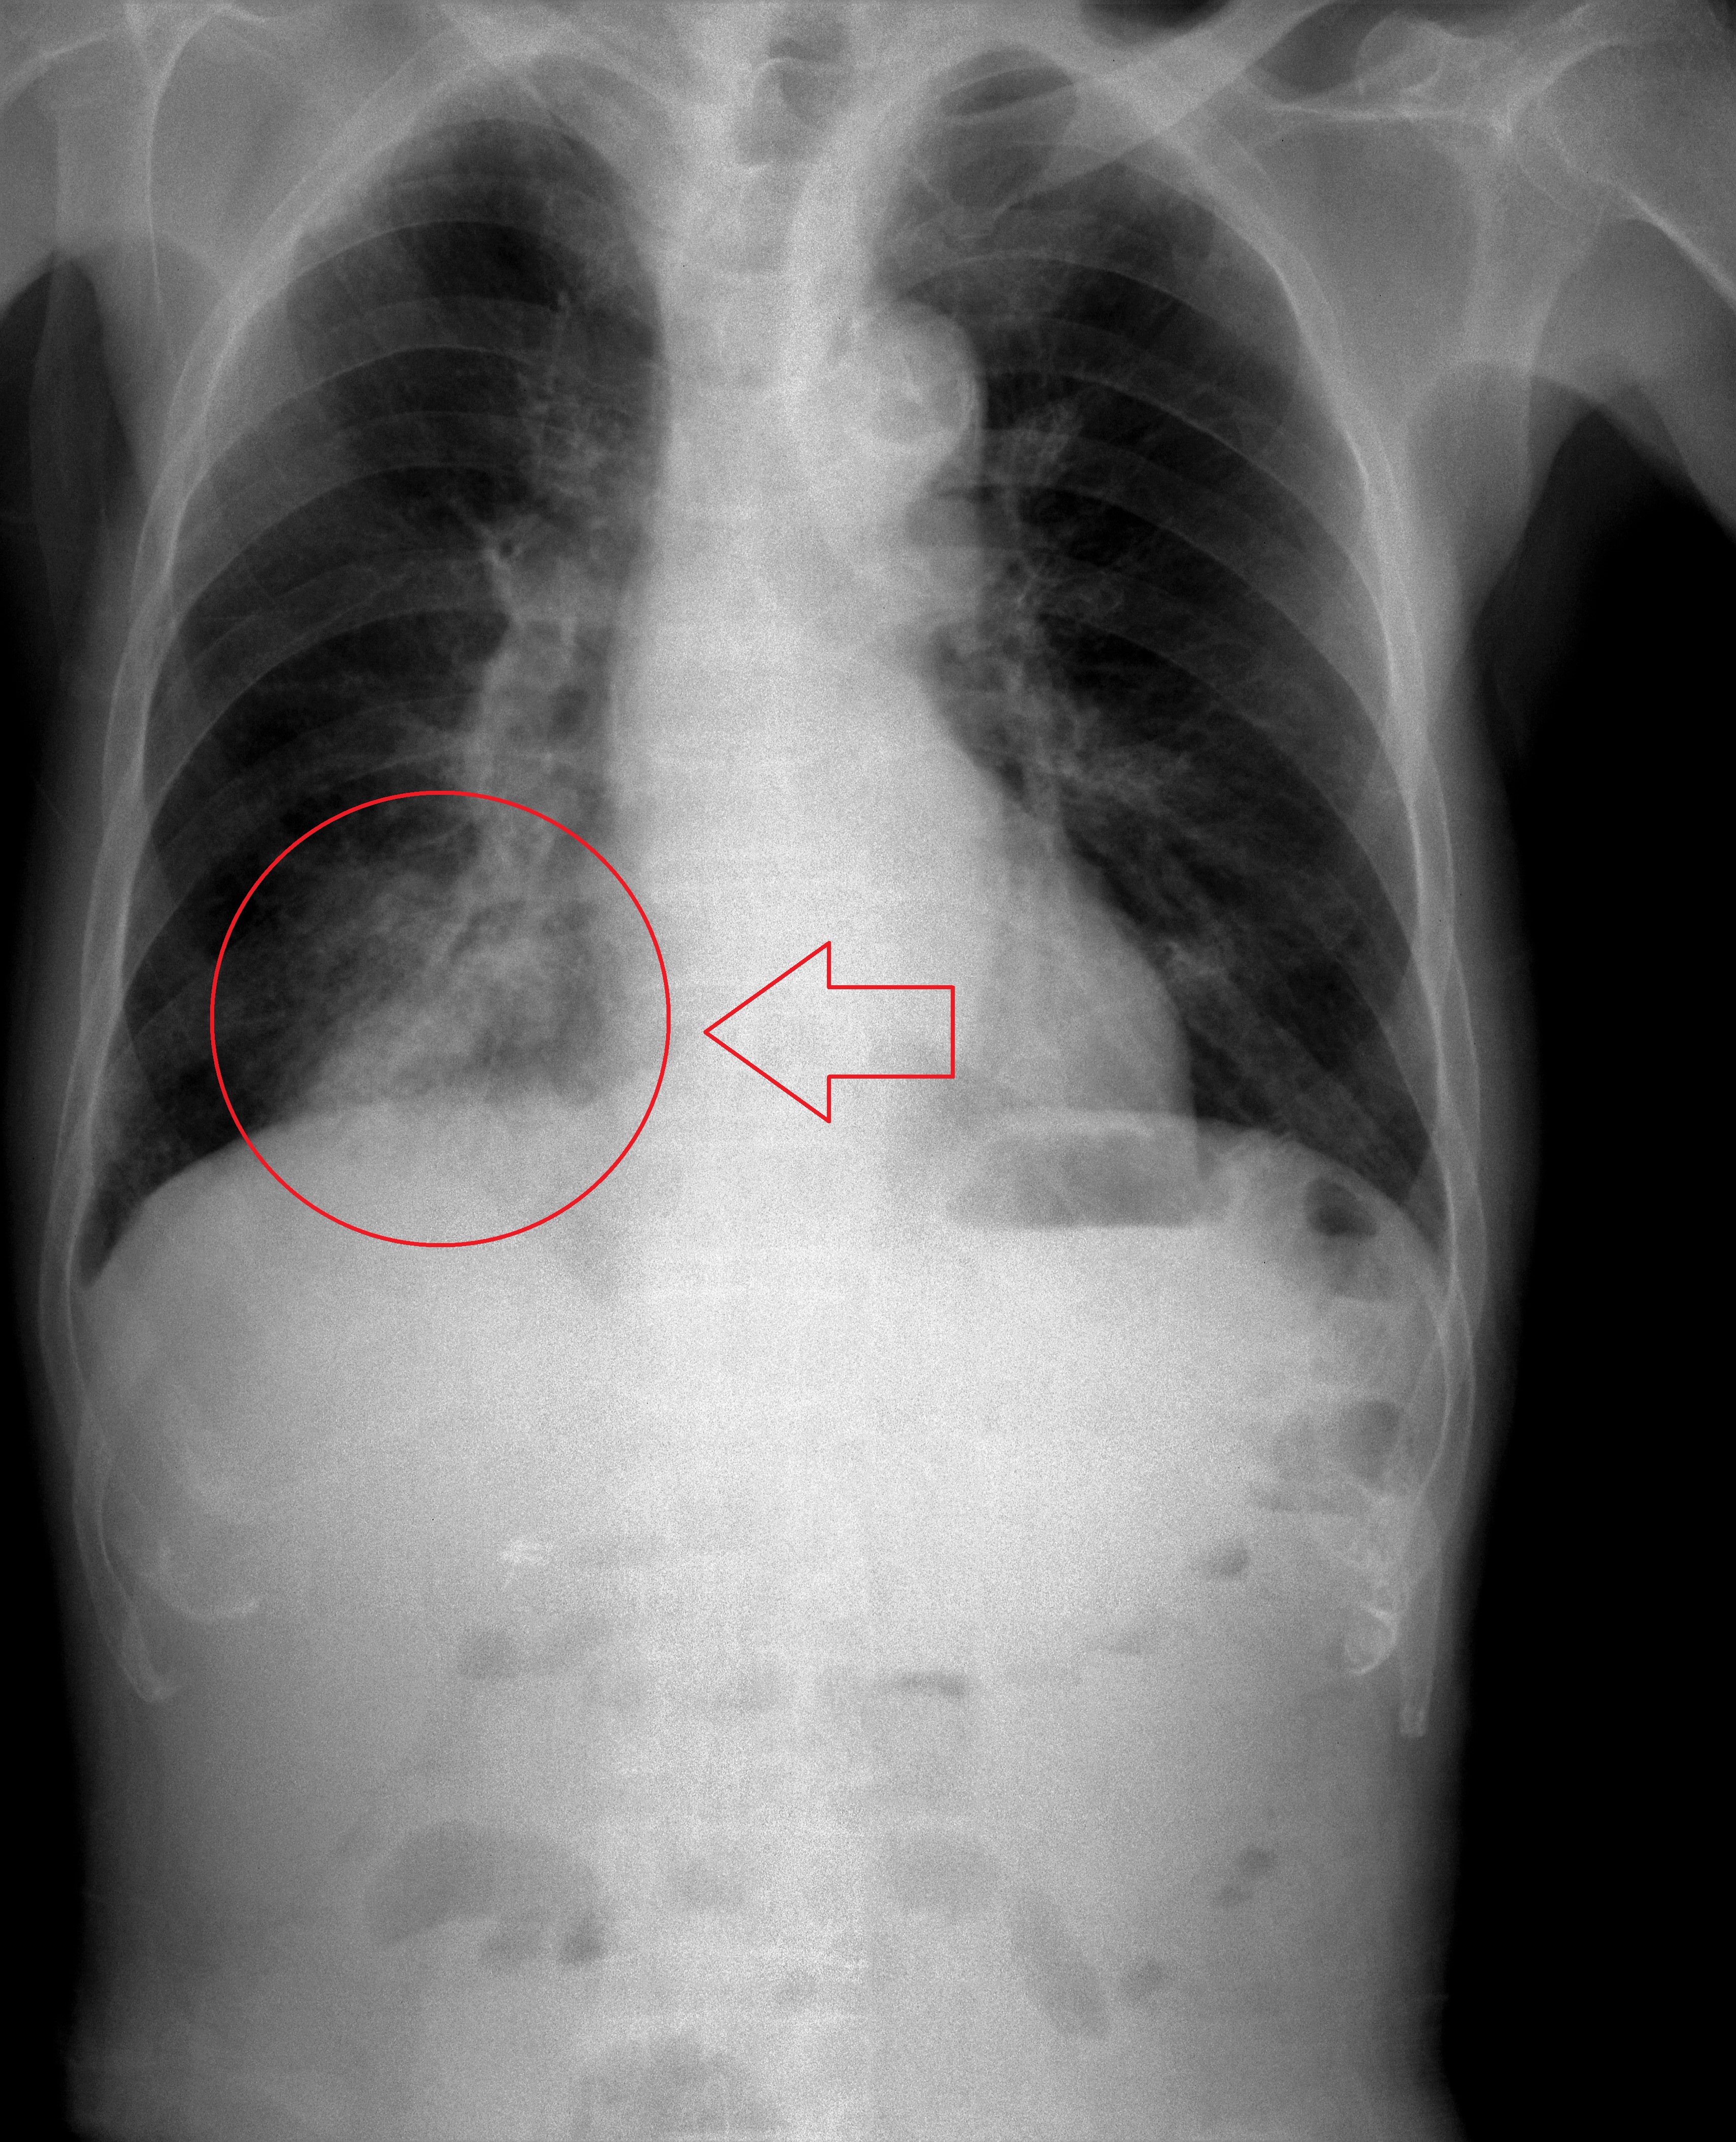

흉부 X-레이는 흡인성 폐렴 진단에 유용할 수 있지만, 초기에는 음성으로 나타날 수 있다.[12] 흉부 CT 스캔 또한 폐렴의 존재를 확인할 수 있으며, 농양, 이물 또는 흉막 질환의 특성 파악에도 도움이 될 수 있다.

투시경 검사 연하 검사는 연하곤란 또는 운동 장애가 흡인의 원인으로 생각되는 경우에 수행할 수 있다. 음식과 음료를 바륨 조영제와 혼합하여 X-레이를 사용하여 연하를 평가한다. 조영제가 성대 아래로 기관으로 흘러 들어가는 경우 흡인으로 진단할 수 있다.[13]